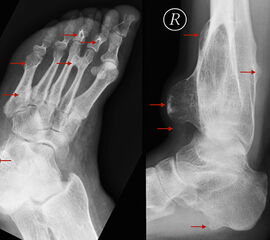

Metastasen finden sich in den distalen Abschnitten der Extremitäten deutlich seltener als in den proximalen (Abb.29 und 30). Am Fuß sind Metastasen somit vergleichsweise selten anzutreffen (<1%). Lungenkarzinome stellen hierbei den häufigsten Primärtumor dar 48 (Abb.31).

Stellvertretend für gutartige tumoröse Weichteilgeschwulste soll hier die pigmentierte villo-noduläre Synovialitis (PVNS) als wohl häufigste gutartige Weichteilneoplasie des Fußes erörtert werden. Die PVNS nimmt als einzige Entität in allen größeren Studien zu Fußtumoren einen der drei vorderen Plätze ein. Als Synonym der extra-artikulären Form der PVNS ist der Begriff des teno-synovialen Riesenzelltumors gebräuchlich. Die sehnenscheiden- und gelenkkapselreiche Fußanatomie prädestiniert für die Entstehung einer PVNS (Abb. 32). Das weibliche Geschlecht ist doppelt so häufig betroffen, das bevorzugte Alter liegt zwischen 30-50 Jahren. Eine schmerzlose, nur langsam größenprogrediente Schwellung ist das häufigste Symptom. Die Rezidivrate wird mit bis zu 30% angegeben 49. Bei der PVNS handelt sich um einen fibro-histiozytären Tumor (echte Neoplasie) und nicht wie ehemals angenommen um ein inflammatorisches oder posttraumatische Geschehen. Für die intraartikuläre Form, die wiederum in eine noduläre/lokalisierte und diffuse Form unterteilt werden kann, stellt das Sprunggelenk die dritt-häufigste Lokalisation am gesamten Körper dar (Abb. 33).

Im Röntgen zeigt sich gelegentlich eine gut abgrenzbare Weichteilformation (bei nodulärer Form) und knöcherne Druckarrosionen der angrenzenden Knochen. Sekundäre arthrotische Veränderungen der angrenzenden Gelenke sind möglich. Die MRT kann mit einem stark T2-gewichtetem Gradientenecho sog. Suszeptibilitätsartefakte der Hemosiderin­ablagerungen darstellen. Diese führen gewöhnlich zu charakteristischen Signalaus­löschungen in T1 und T2 gewichteten Sequenzen. Eine Kontrastmittel-Aufnahme erfolgt in der Regel diffus und inhomogen. Die Therapie besteht in einer offenen Resektion. Wir raten dringend davon ab, intraartikuläre, lokalisierte Formen der PVNS per Arthroskopie resezieren zu wollen. Dieser Tumor sollte, wenn möglich, marginal und nicht intraläsional reseziert werden. Eine arthroskopische Zerkleinerung mit dem Shaver würde aus einer nodulären Form eine diffuse Form produzieren und die Rezidivwahrscheinlichkeit deutlich steigern. Ebenso ist vor einer Radiosynoviorthese (RSO) bei Vorliegen einer nodulären Variante abzuraten. Bei diesem nuklearmedizinischen Verfahren, welches gewöhnlich Anwendung bei chronisch entzündlichen Gelenkerkrankungen findet, werden Beta-Strahler in Gelenke injiziert. Ein therapeutischer Effekt hat sich bisher nicht nachweisen lassen.